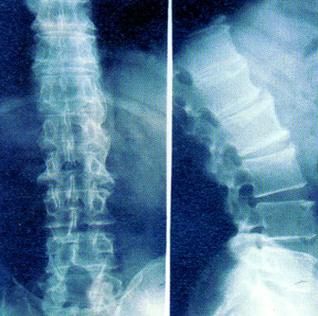

强直性脊柱炎又名类风湿脊柱炎。本病为脊柱各关节及关节周围组织的侵袭性炎症。一般先侵犯骶髂关节,其后由于病变发展逐渐累及腰椎、胸椎和颈椎,出现小关节间隙模糊、融合消失及椎体骨质疏松破坏、韧带骨化,终致脊柱强直或驼背固定。主要症状为发病部位疼痛,活动受限。是一种病因不明的常见病。

强直性脊柱炎症状: 起病缓慢,全身症状轻微,早期可有倦怠,体征减轻,或有恶心、发热等。逐渐出现下腰部疼痛,肌肉痉挛及僵硬,休息后症状往往加重,活动后减轻。以后逐渐出现典型的骶髂关节疼,并呈上行性累及脊柱,受累部位疼痛、压痛、僵硬、活动受限,并逐渐出现屈曲畸形,阴天或劳累后症状加生,遇暖或休息后减轻。常有复发性虹膜炎并存,部分患者可出现坐骨神经痛。病变若波及肋椎关节,还可出现呼吸时胸部扩张受限或丧失以及肋间神经痛等。 晚期患者脊柱强直在畸形位,颈腰部不能旋转,侧视时必须转动全身,可出现严重的驼背畸形,不能前视。病变有时也可波及髋膝关节,髋关节受累时,呈摇摆步态。随着受累部位的骨性强直,疼痛等症状逐渐消失,而遗留终生畸形。相关推荐: 治疗强直性脊柱炎的三个难点

什么是强直性脊柱炎? 强直性脊柱炎是一种很古老的疾病,早在几千年前的古埃及人的骨骼就发现有强直性脊柱炎的证据。以往曾认为强直性脊柱炎是类风湿性关节炎的中枢型,但随着医学的发展,检测手段的提高,发现该病与类风湿性关节炎有很大的区别,故将其定为一种独立性疾病。 现代医学认识到,强直性脊柱炎是一种慢性、进行性和炎性疾病,病变部位主要在骶髂关节、脊柱、脊柱旁软组织及四肢关节。该病变常自骶髂关节开始,逐渐向上蔓延到脊柱及脊旁组织,后引起骨性强直。目前认为本病是一种结缔组织的血清阴性关节病,是较常见的腰背痛疾病之一。